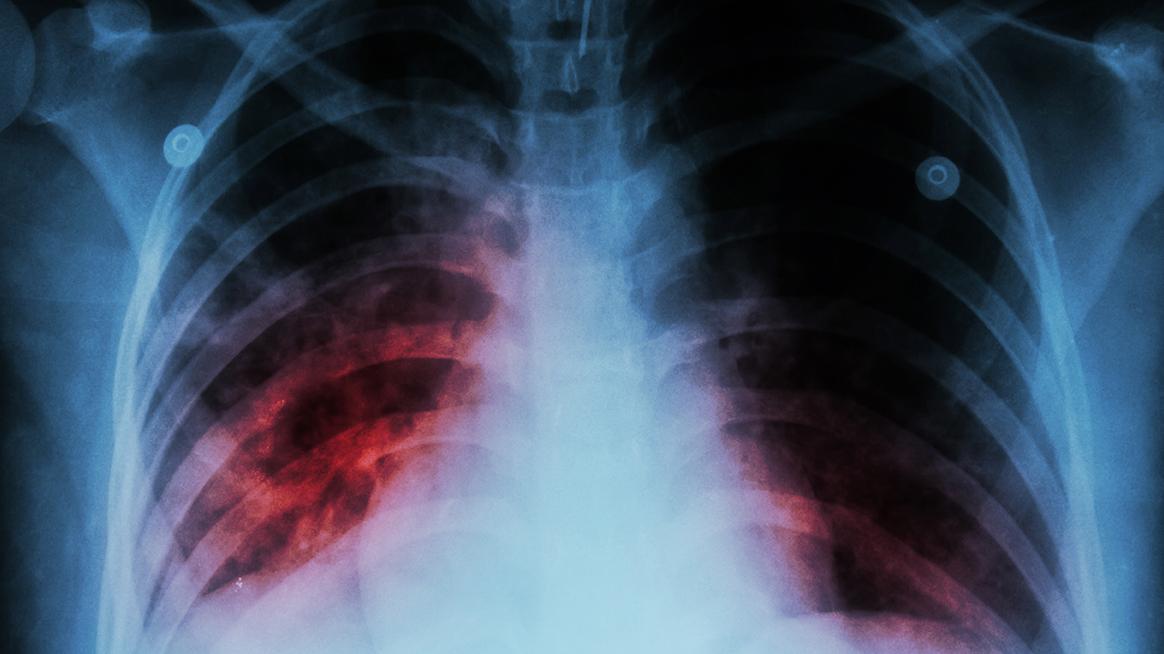

Новите случаи на туберкулоза по света са се увеличили за първи път от над две десетилетия, като за това е допринесла пандемията от КОВИД-19, възпрепятствайки същевременно усилията за справяне с болестта, съобщават световните осведомителни агенции, позовавайки се на доклад на Световната здравна организация (СЗО).

Миналата година около 10,6 милиона души са заболели от туберкулоза - увеличение с 4,5 процента спрямо предходната. Болестта се причинява от бактерия, която атакува предимно белите дробове.